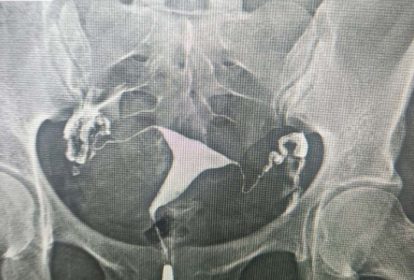

Chụp X quang tử cung – vòi trứng (còn được gọi X quang vòi trứng, tên tiếng Anh Hysterosalpingography – HSG) là kỹ thuật chẩn đoán hình ảnh dùng để đánh giá tình trạng tử cung và ống dẫn trứng. Phương pháp được thực hiện bằng cách bơm dung dịch cản quang vào buồng tử cung, sau đó chụp X quang để quan sát toàn bộ hình dạng, cấu trúc buồng tử cung, đồng thời cung cấp các thông tin bất thường, tổn thương ở ống dẫn trứng như tắc, hẹp một hay hai ống dẫn trứng, vị trí đoạn tắc ở gần hay xa hoặc có ứ dịch vòi trứng hay không.

Các số liệu thống kê cho thấy nguyên nhân vô sinh nữ chiếm khoảng 40%. Nguyên nhân gây vô sinh có thể do bệnh lý tử cung, buồng trứng, ống dẫn trứng, di truyền và bệnh lý hệ thống, trong đó vô sinh liên quan ống dẫn trứng chiếm 35-40%. Việc phát hiện sớm, đánh giá bất thường ống dẫn trứng sớm là phần quan trọng trong chẩn đoán vô sinh. Đây là tiền đề quan trọng để bác sĩ đưa ra phác đồ điều trị phù hợp, tối đa cơ hội mang thai thành công.